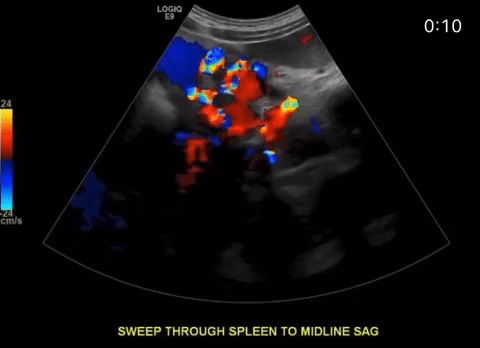

When the portal vein enters the liver it bifurcates into right and left main branches. The right portal vein bifurcates into an anterior and posterior branch which feed segments 5, 6, 7 and 8 respectively, whereas the left branch feeds segments 2, 3 and 4. The normal diameter of the main portal vein is 1.3 cm (some institutions use 15. as the upper limit) Normal flow is hepatopetal (towards the liver), with a flow velocity between 15-40 cm/s. Be sure to make sure you color is inverted and your approach is optimized. In the main portal vein below flow is hepatopetal in both images, the only difference is transducer angle, tilt and approach.

Approximately 25% of cirrhotic patients can develop portal vein thrombosis, Oftentimes due to portal hypertension and sluggish flow through the fibrotic liver. Stagnant blood flow is more prone to coagulation. Any hypercoagulable condition can lead to portal vein thrombosis. (i.e. cancer, pregnancy, coagulopathies, COVID 19 to name a few).

Many people diagnosed with PVT are asymptomatic, some patients may have ascites, abdominal pain, hepatosplenomegaly, blood in the stool, bloody emesis (from ruptured varices). When the thrombus causes portal hypertension or if there is portal hypertension form cirrhosis, portosystemic collaterals may form. These sites of include: